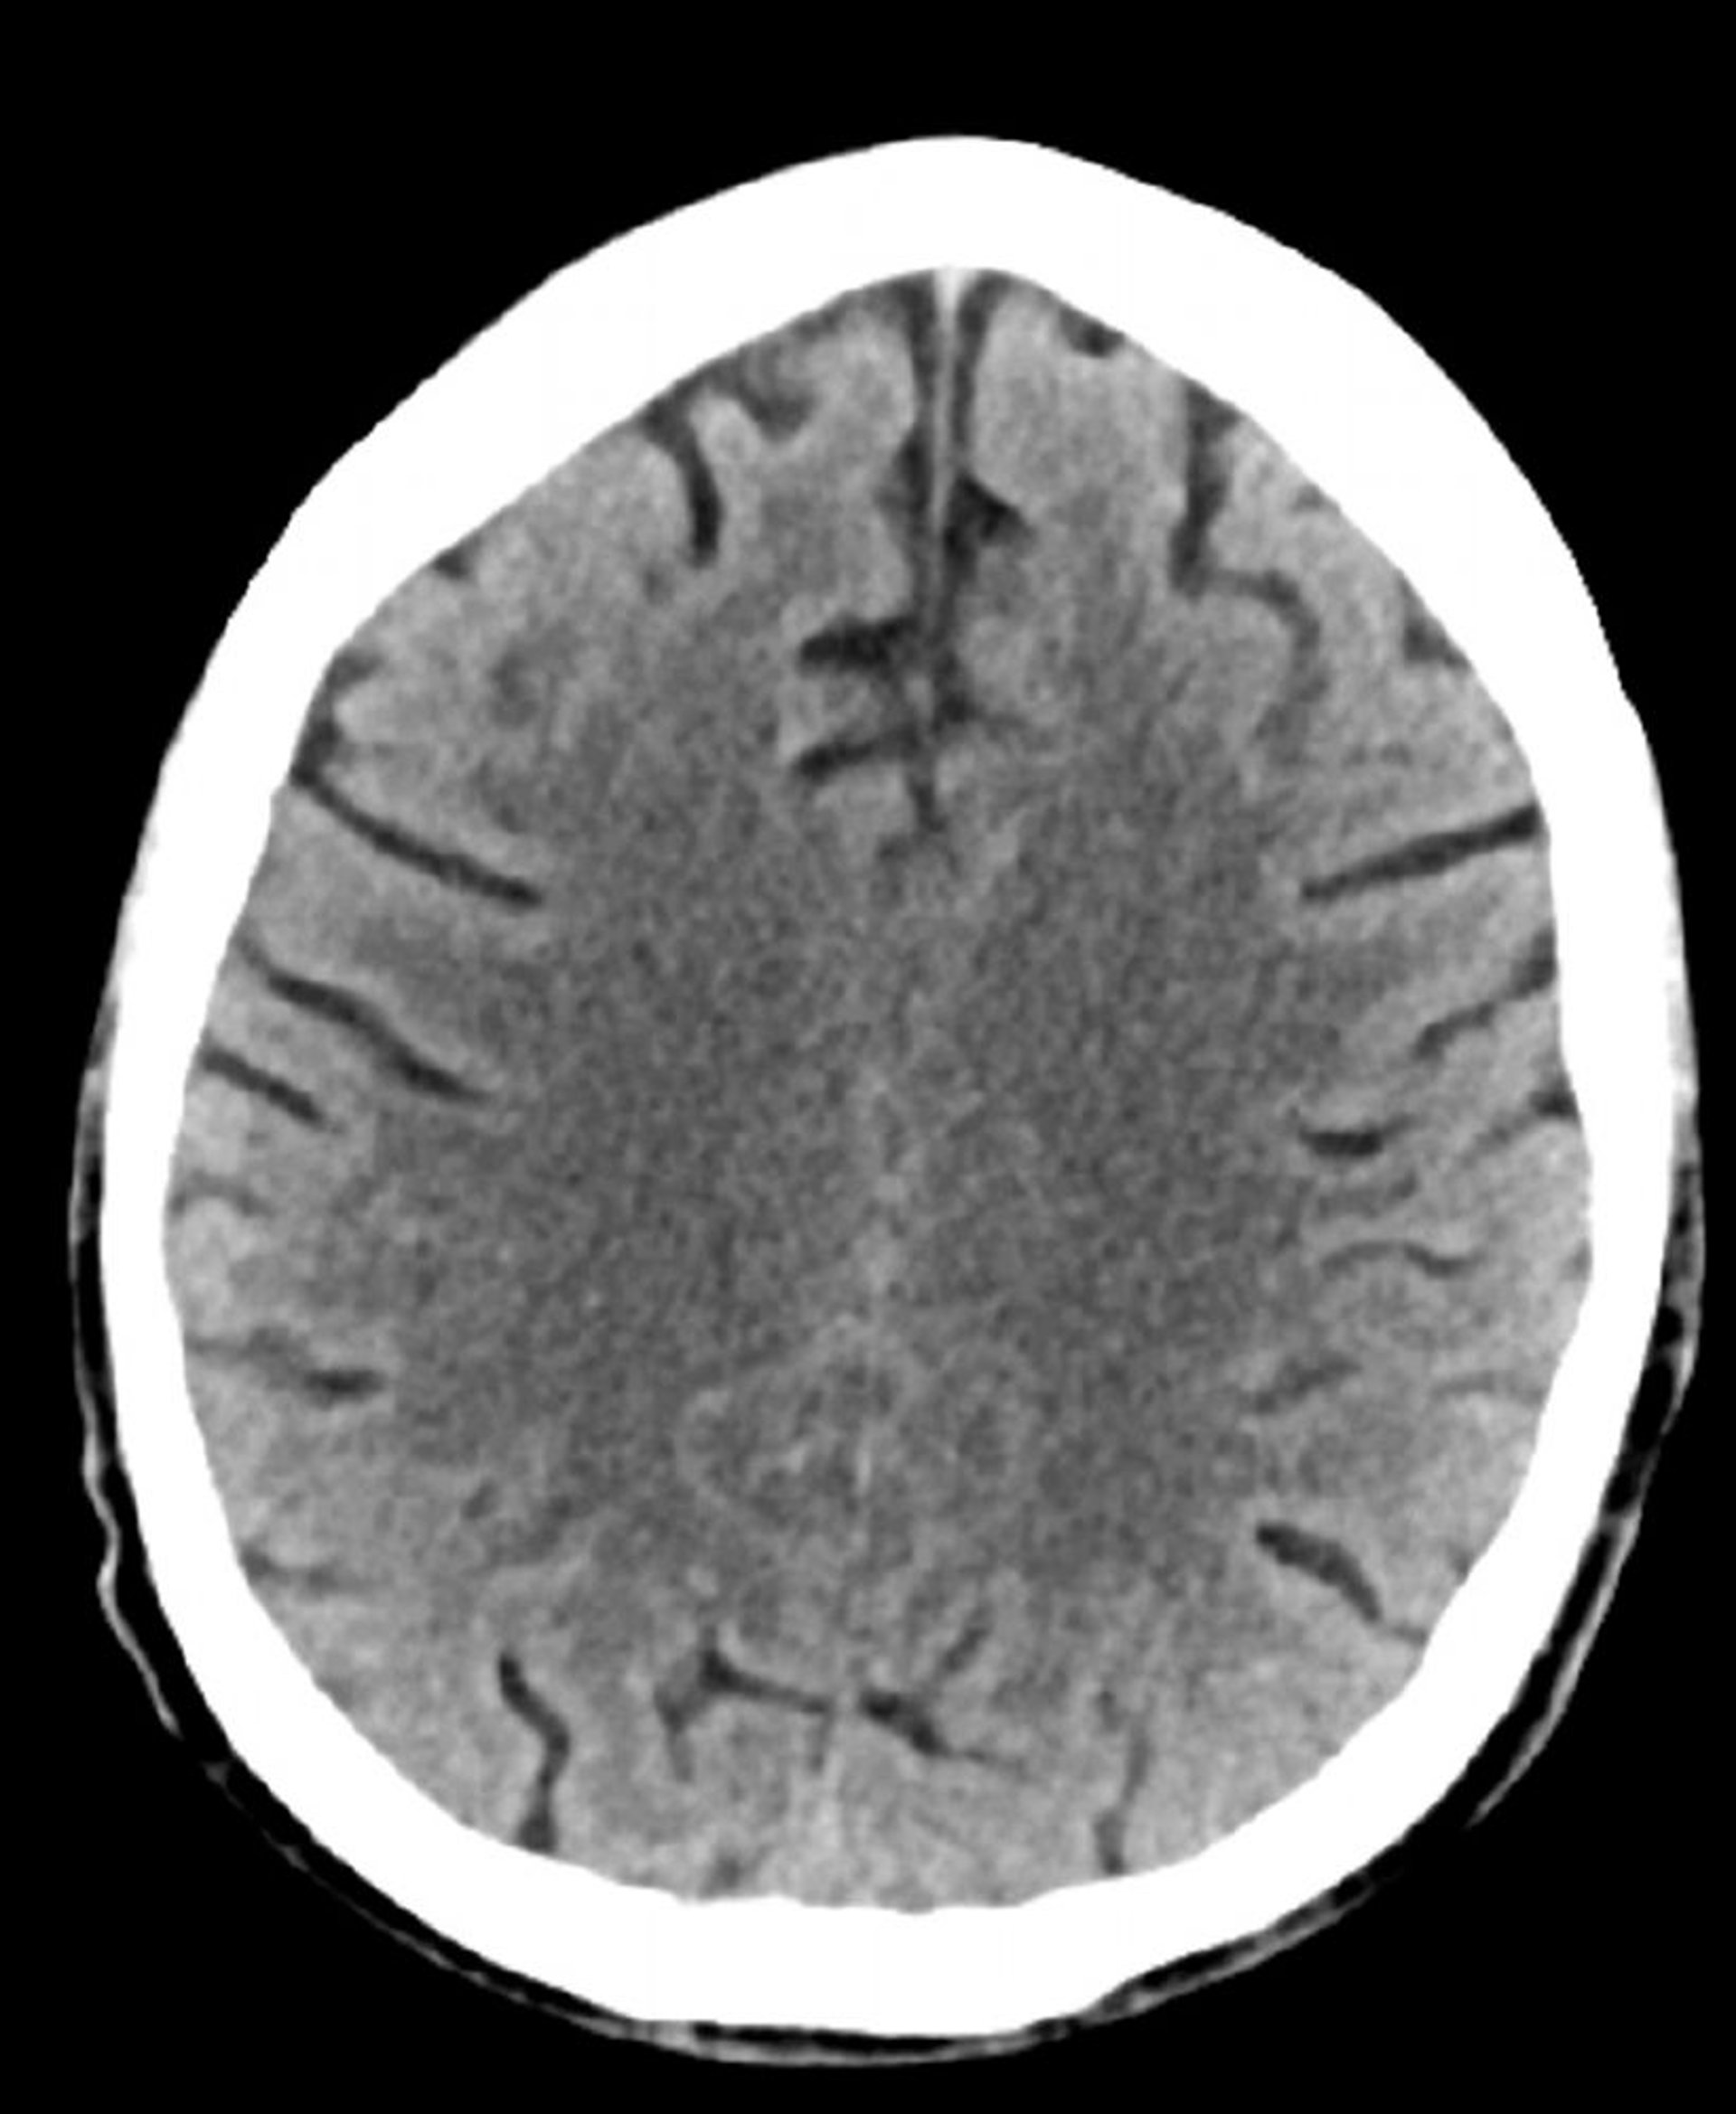

Tomografía computarizada craneal normal (adulto, 74 años)–diapositiva 2

Esta imagen es una tomografía computarizada craneal normal correspondiente a un adulto de 74 años. Cuando se compara con la TC normal de la cabeza de un paciente de 30 años, los surcos son más grandes. Estos son hallazgos normales en este grupo de edad.